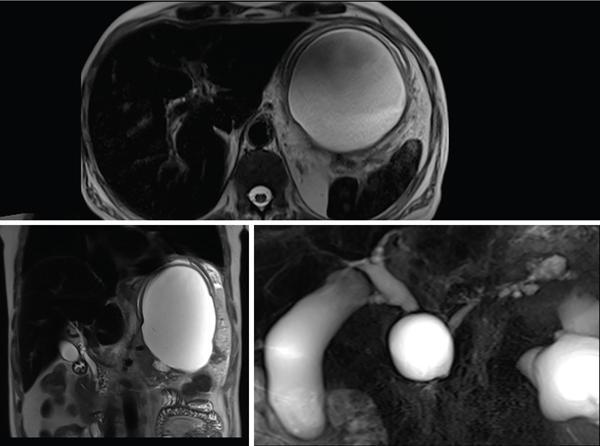

Anirudh Kohli Acute pancreatitis is one of the most dreaded diseases to afflict mankind, in view of its high morbidity and mortality. The single most important factor in reducing the morbidity and mortality of this condition over the last many years has been the role of computed tomography (CT). The incidence of acute pancreatitis is rising especially due to an increasing incidence of gallstones, obesity, as well as an ageing population. Pancreatitis occurs due to a chain of events triggered by a temporary/permanent pancreatic duct obstruction. This leads to activation and release of pancreatic enzymes into pancreatic interstitium and peripancreatic tissues leading to severe auto digestion and necrosis of pancreas and adjacent tissues. Systemically there is release of inflammatory mediators known as cytokines. Tumour necrosis factor is a cytokine which is toxic to acinar cells. These cytokines activate and intensify the inflammatory cascade that may ultimately culminate in multiorgan failure. Clinically severe acute pancreatitis is characterized by two phases, an early phase and a late phase. The early phase is dominated by the systemic effects of release of inflammatory mediators such as cytokines – termed as systemic inflammatory response syndrome (SIRS). Usually there is associated variable multiorgan dysfunction/failure. This phase lasts for a week. When the multiorgan failure lasts 2 days it is termed as mild, multiorgan failure lasting more than 48 hours is considered severe. There is no correlation between the clinical severity of pancreatitis and morphological changes in this early stage. In view of this CT scan is not of much utility during this phase, unless complications are suspected. The later phase is dominated by effects of local complications due to pancreatic/peripancreatic necrosis. Mortality follows this biphasic pattern in early weeks from the systemic effects of multiorgan failure and in later weeks due to local effects, for example infection of necrotic pancreatic/peripancreatic tissues superimposed by organ failure. The Clinical diagnosis of acute pancreatitis requires two of the following three features: If the first two findings are present without any significant SIRS then CT is not required. Acute pancreatitis is a complex disease with a wide variation in the presentation and outcome, ranging from asymptomatic with only biochemical alterations to a fatal outcome. In fact acute pancreatitis is a dynamic disease with continuously evolving appearances on imaging. There are two distinct forms of acute pancreatitis – interstitial oedematous pancreatitis and acute necrotising pancreatitis. Interstitial oedematous pancreatitis is a condition where there is only mild swelling of the pancreas with loss of normal lobulations and a diffuse decrease in attenuation of the pancreas. There may be heterogeneity of the pancreatic parenchyma due to varying degrees of interstitial oedema. This form of pancreatitis runs a mild course and rarely progresses to acute necrotising pancreatitis with its associated complications. In a third of these cases the pancreas may reveal no abnormality on a CT scan. The inflammatory changes may be restricted to the pancreas or extend into the peripancreatic regions. The inflammation in the peripancreatic regions manifests as acute pancreatic effusions. If there is peripancreatic fat necrosis with an oedematous pancreatic gland it is termed as acute necrotising pancreatitis (Figs. 9.17.1–9.17.2). Acute pancreatic fluid collections are enzyme-rich pancreatic juice collections seen in about 40% of patients with acute pancreatitis. The fluid collections occur due to exudation of pancreatic juices into the interstitium of the pancreas and subsequently leakage into the surrounding tissue spaces. These fluid collections are localized only by the anatomic space in which they collect. As the exudative process continues, the parietal peritoneum overlying the pancreas may be disrupted with the inflammatory fluid entering the lesser sac. From the lesser sac the fluid can enter the peritoneal cavity via the foramen of Winslow or by dissecting the peritoneum along the anterior surface of the lesser sac. Posterior extension of the fluid collection in the anterior pararenal space may occur into a potential space between the laminae of the posterior pararenal fascia. Rarely there may be involvement of the perirenal and posterior pararenal spaces. Other pathways of dissection are along the gastrohepatic, gastrosplenic and gastrocolic ligaments. Fluid may dissect along the root of the mesentery into the transverse mesocolon. Collections may extend around the caecum, ascending colon, descending colon and into the lumbar, pelvic and inguinal regions. Large fluid collections may dissect superiorly into the mediastinum or pericardial space. The quantity of fluid in these effusions is variable and can range from a small amount to large quantities (Fig. 9.17.3). Of these collections, 50% resolve spontaneously; the remainder may evolve after 4–6 weeks into pseudocysts. As the collections age, they tend to get localized and walled off, often developing an enhancing wall. A collection should be termed a pseudocyst only when a definite capsule develops and the collection has been static for at least 4–6 weeks. The risk of complications such as rupture, infection and haemorrhage increases with the age of the collection. Large collections of fluid are usually associated with a lesser degree of pancreatic necrosis as compared to extensive pancreatic necrosis associated with a lesser amount of fluid collection. Acute necrotising pancreatitis is a fulminant form of pancreatitis in which there is necrosis of the pancreas, that is nonviable pancreatic tissue. A contrast-enhanced CT is essential as it is the ideal means to demonstrate necrosis as well as to determine the extent of necrosis. These areas of nonviable pancreatic tissue do not enhance as compared to viable pancreatic tissue, which demonstrate significant enhancement. The extent of pancreatic necrosis has been found to correlate extremely well with the extent of necrosis found at surgery. The size, location and extent of pancreatic necrosis are very variable. These areas may be diffuse or focal, small in size to complete glandular involvement. These necrotic areas have a very important bearing on the course of pancreatitis, as they are liable to undergo secondary infection and form pancreatic sepsis. In addition, the more extensive the pancreatic necrosis the greater is the morbidity and mortality. Patients with no pancreatic necrosis have been found to have a 0% mortality and a 6% complication rate, whereas patients with pancreatic necrosis have a 23% mortality rate and an 82% complication rate. A variety of laboratory tests are available to detect pancreatic necrosis, such as a rise in the serum methemalbumin, quantitative estimation of C-reactive protein and urinary trypsinogen-activated peptide. CECT is still the most accurate modality to detect pancreatic necrosis. Pancreatic necrosis may be seen in the pancreas only, peripancreatic tissues also or only in the peripancreatic region. Isolated peripancreatic necrosis occurs due to disruption of the peripheral ductules with extravasation of activated pancreatic enzymes, may be seen in up to 20% of patients who require operative/interventional management of their necrotising pancreatitis. These patients with only peripancreatic necrosis have a better prognosis. This essentially represents retroperitoneal fatty tissue necrosis appearing as heterogeneous areas of liquid and nonliquid components. Over time necrosis evolves and liquefies as well as the liquid component resorbs. Generally if the liquid component is 2 cm or less it will resorb, while fluid collections 5 cm or more rarely resorb. If pancreatic necrosis is not resorbed it may get walled off or with time or may become infected. Encapsulation occurs between the third and fourth weeks. It is important to differentiate sterile from infected necrosis as sterile necrosis rarely needs surgery, whereas infected necrosis requires long-term antibiotic therapy and/or some kind of imaging/surgical intervention. According to the Atlanta 2012 classification, all areas of pancreatic necrosis are termed as acute necrotic collections. This represents a combination of pancreatic/peripancreatic fat necrosis with peripancreatic effusions. On CT, there is a spectrum of findings – solid, liquid containing debris (these may be nonwalled off/partially walled off). Sonography and MRI have advantages over CT scan in demonstration if the contents are pure liquid such as acute pancreatic effusions or have some nonliquefied components such as acute necrotic collections. Pseudocysts are round or oval encapsulated fluid collections containing only liquefied components. It takes 4 weeks for the granulation tissue to develop. On CT, a pseudocyst appears as a well-defined fluid collection with a thin capsule. The most common location for pseudocysts is the lesser sac, though they may be found anywhere in the mediastinum, abdomen or pelvis as they may dissect along fascial planes, along vessels and through capsules of solid organs. Pseudocysts in the bowel, though reported, are relatively rare, as the bowel wall is a strong barrier to the effect of proteolytic pancreatic enzymes. When the contents of the pseudocyst are heterogeneous or uniformly increased in attenuation, the possibilities of infection or haemorrhage should be considered. Focal areas of increased density within the fluid collection usually indicate haemorrhage. Complicated, enlarging or symptomatic pseudocysts require percutaneous catheter or surgical drainage. Infected pseudocysts are treated by percutaneous drainage. The management of a noninfected pseudocyst is controversial. Surgical treatment is only undertaken when the wall is mature after several weeks. Large pseudocysts greater than 5 cm in size can easily be drained percutaneously using intercostal drainage tube or pigtail catheter or endoscopically via the stomach. The cure rates are reported to be 85% with percutaneous drainage, the drainage period averaging about 20 days (Figs. 9.17.4–9.17.5). Walled off necrosis – as pancreatic/peripancreatic necrosis matures and evolves, an interface develops between necrosis and adjacent fatty tissue and an enhancing thickened wall is seen, resulting in a well-defined fluid collection with necrotic debris and fat necrosis. This is the end stage in the evolution of an acute necrotic collection. It is important to differentiate a pseudocyst from walled off necrosis, as a pseudocyst requires drainage and walled off necrosis requires surgical removal (Figs. 9.17.6–9.17.9). Sepsis is a major complication of pancreatitis and is accompanied by a high incidence of mortality and a prolonged hospital stay. Pancreatic sepsis may occur following secondary infection of pancreatic and/or peripancreatic necrosis, acute pancreatic fluid collections and pseudocysts. The only specific sign to demonstrate sepsis is the presence of gas in a collection. This occurs due to secondary infection by coliform/anaerobic organisms. This sign is unfortunately not common and seen in only one-third of cases. Gas is seen in the fluid collection as very dark well-defined air attenuation bubbles. Occasionally gas may be present due to a gastrointestinal fistula or previous surgery. Fat necrosis is seen in peripancreatic collections. This should not be confused with air bubbles, which are indicative of sepsis. The differentiation is easy to understand by CT, the values of fat ranging between – 20 HU and – 80 HU, and of air being >–300 HU. Also air bubbles have well-defined margins and are homogeneously jet black, whereas fat is nonhomogeneously grey with ill-defined margins. Since the presence of air is seen only in a small percentage of patients with pancreatic sepsis, the only other means to diagnose pancreatic sepsis is by CT-guided aspiration. All sites of fluid collection, parenchymal necrosis and peripancreatic necrosis are subjected to CT-guided aspiration. This is a tedious process and requires a dedicated interventional radiologist as there are often more than 5–6 sites from which it may be necessary to obtain samples. A fresh needle and syringe are used for each site, as it is important to know which site has sepsis and which is sterile. Care is taken not to transgress the large bowel as the colon has a large number of bacteria, and transgressing it could result in colonic bacteria contaminating the CT-guided aspiration sample, with falsepositive results. Further, colonic bacteria may be inoculated into a sterile acute pancreatic fluid collection or necrosis thereby converting a sterile collection into an infected one (Fig. 9.17.10). Complications of the procedure can be pneumothorax if the pleura is transgressed, haemorrhage due to trauma to a vessel, and secondary infection. Pancreatic sepsis is treated by surgical debridement, necrosectomy and drainage through thick tubes. It is crucial from the management point of view to differentiate an abscess from infected necrosis. An abscess may be treated by percutaneous drainage, whereas infected necrosis developing in relatively solid tissue can be treated by surgical debridement alone. Imaging-guided percutaneous drainage is the first step in treating pancreatic sepsis especially patients who are very ill and cannot undergo surgery. Initially pig tail catheters were used but these are notorious to get blocked as the largest bore of a pigtail catheter is 12 F. Pancreatic sepsis contains a large amount of necrotic debris, this blocks the catheters can be cleared by flushing the catheter, but this always raises the possibility of introducing secondary infection. To circumvent this issue large-bore ICD catheters have been introduced. These range from 16 F to 30 F. A safe window is necessary, not transgressing bowel or vasculature. It is quite easy to insert these tubes percutaneously under CT. A bit of initial manipulation and force is required to pierce the abdominal musculature. These large-bore drainage tubes have been very effective unless the infected necrosis is solid with minimal liquefied contents or a safe window for placing an ICD catheter is not available. CT is also invaluable in surgical planning and in the follow-up of postoperative patients to evaluate any fresh collection and also to determine whether the drains are well sited or not (Fig. 9.17.11).